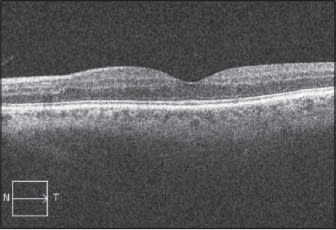

Figure 2. Preoperative SD-OCT (left ) shows significant macular edema with cystoid fluid accumulation in a patient with background DR. A one-month posoperative SD-OCT image (right) shows significant improvement in macular thickness and resolution of the cystoid spaces.